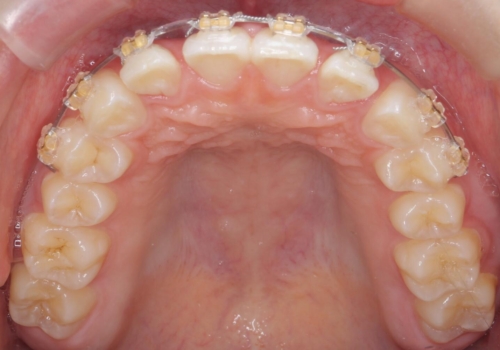

- ワイヤー矯正

全体矯正ではなく部分矯正で治療することになりました。

その代わり、すき間をすべて閉じるのは難しく、両脇の目立たないところに集めて治療終了しています。